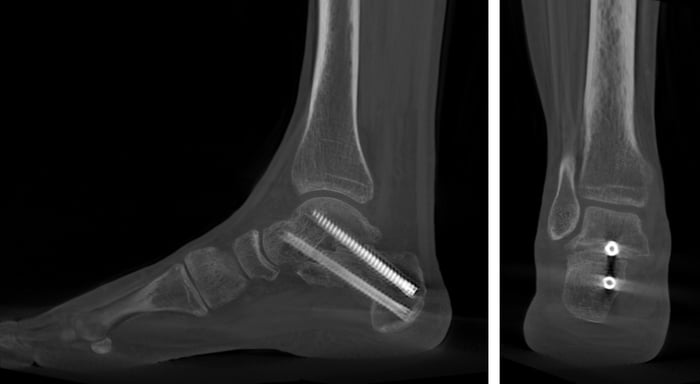

Queste vengono stabilizzate con mezzi in titanio anallergico e consentono carico immediato dopo l’intervento.

3. Artrodesi

Quando il piede è molto rigido o la deformità è estrema, la soluzione è l’artrodesi. In questo caso si blocca l’articolazione tra calcagno e astragalo, limitando i movimenti di inversione ed eversione ma preservando la flessione e l’estensione della caviglia.